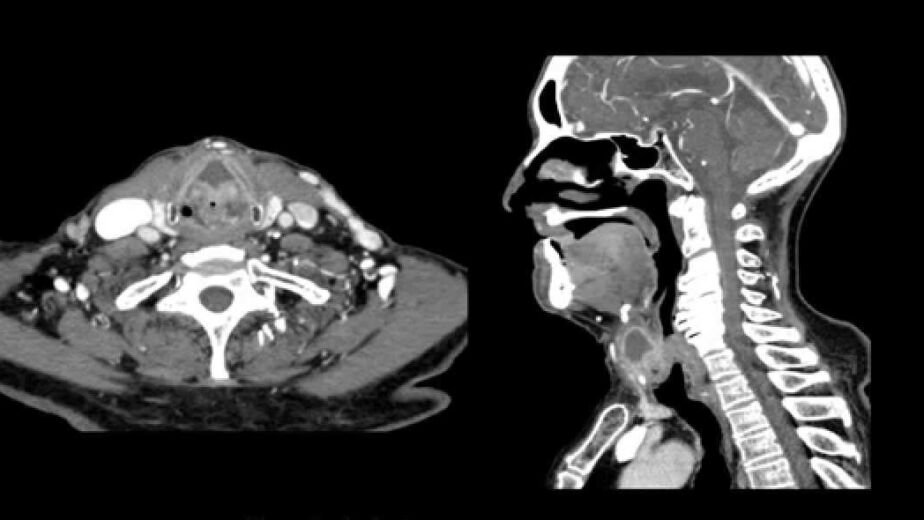

La tomografía axial computarizada (TAC) es una técnica de imagen médica que utiliza rayos X para crear imágenes detalladas de estructuras internas del cuerpo. A diferencia de las radiografías convencionales, que ofrecen una visión bidimensional, la TAC proporciona imágenes en cortes transversales, lo que permite a los médicos observar con mayor claridad la anatomía y las posibles anomalías. Este procedimiento implica la rotación de un tubo de rayos X alrededor del paciente, mientras que un detector recoge la radiación que atraviesa el cuerpo.

Los datos obtenidos se procesan mediante un ordenador para generar imágenes tridimensionales que pueden ser analizadas en diferentes planos. El funcionamiento de la TAC se basa en la variación de densidades de los tejidos. Los tejidos más densos, como los huesos, absorben más radiación y aparecen más claros en las imágenes, mientras que los tejidos menos densos, como los músculos y los órganos, se visualizan con menos claridad.

Esta capacidad para diferenciar entre distintos tipos de tejidos hace que la TAC sea especialmente útil en el diagnóstico de problemas cervicales, donde se pueden identificar lesiones, inflamaciones o malformaciones en la columna vertebral y las estructuras circundantes.

Una de las principales ventajas de la TAC en el diagnóstico de problemas cervicales es su capacidad para proporcionar imágenes de alta resolución y gran detalle. Esto es crucial cuando se trata de evaluar condiciones como hernias discales, fracturas vertebrales o tumores en la región cervical. La claridad de las imágenes permite a los médicos realizar un diagnóstico más preciso y, por ende, establecer un plan de tratamiento adecuado.

Además, la TAC es rápida y no invasiva, lo que significa que los pacientes pueden recibir sus resultados en un corto período de tiempo. Otra ventaja significativa es la posibilidad de realizar estudios contrastados. En algunos casos, se utiliza un medio de contraste intravenoso para resaltar estructuras específicas, lo que mejora aún más la visualización de lesiones o anomalías.

Esto es especialmente útil en situaciones donde se sospecha la presencia de tumores o infecciones, ya que el contraste puede ayudar a diferenciar entre tejido sano y patológico. La combinación de rapidez, precisión y capacidad para obtener imágenes detalladas convierte a la TAC en una herramienta invaluable en el diagnóstico cervical.